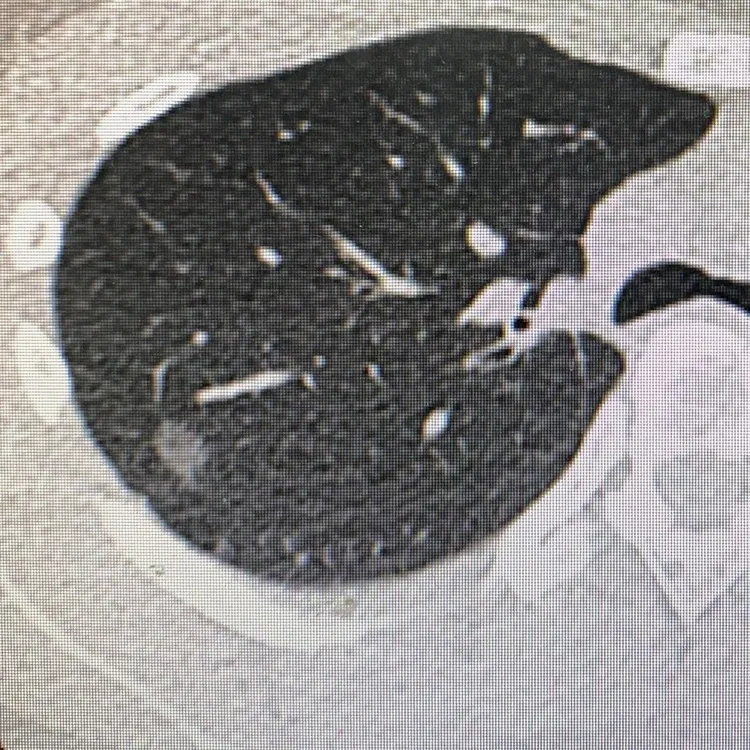

雅薇在個人IG透露,原本她因票選活動被看見感到相當開心,隔天她在自己服務的醫院做健檢,自費加做低劑量肺部電腦斷層(LDCT),做完當下自己用電腦看到一顆充滿敵意的結節,結果醫師告知「這可能惡性」,讓她瞬間晴天霹靂,當天是哭著上班的,一邊流淚一邊處理病人狀況。

經過醫界前輩學姊的開導,她感到能在30歲提早發現已經很幸運,也慶幸今年自己加做LDCT,否則等一般X光檢查看到,可能已經末期,更感謝好朋友常提醒她記得健檢、要做好傷病保險。